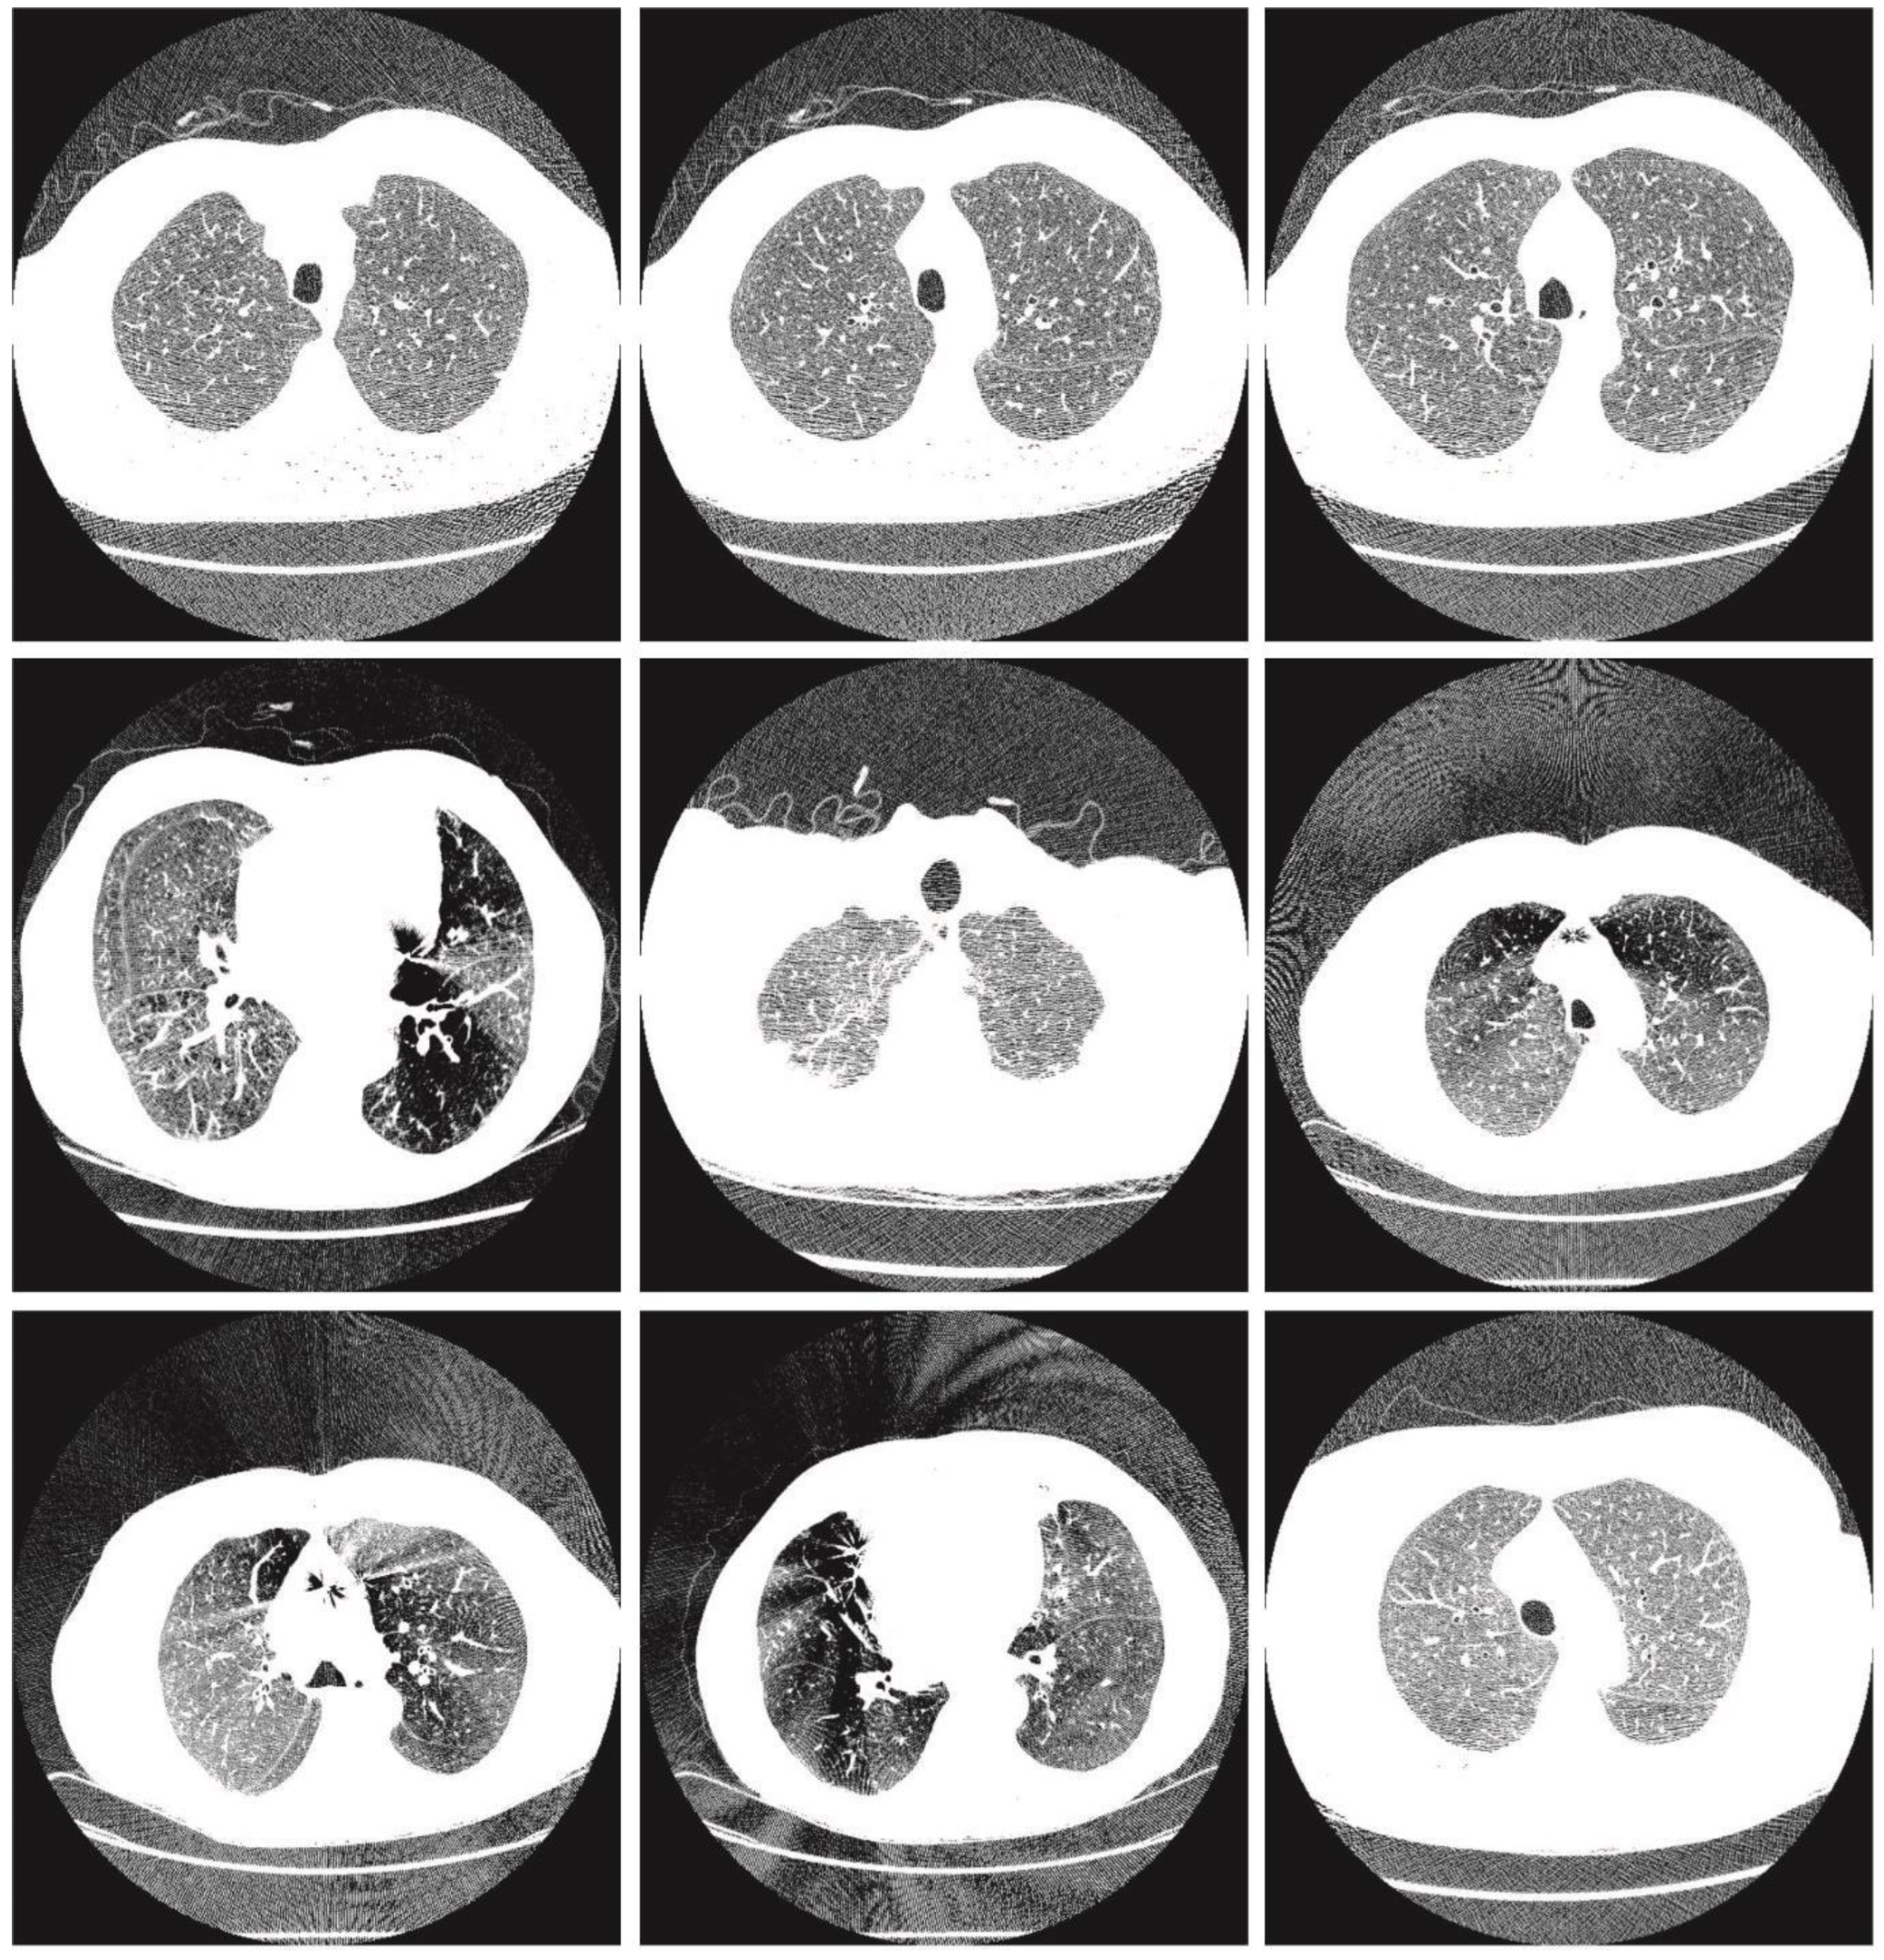

Cat Swarm Optimization-Based Computer-Aided Diagnosis Model for Lung Cancer Classification in Computed Tomography Images

4. Experimental Validation